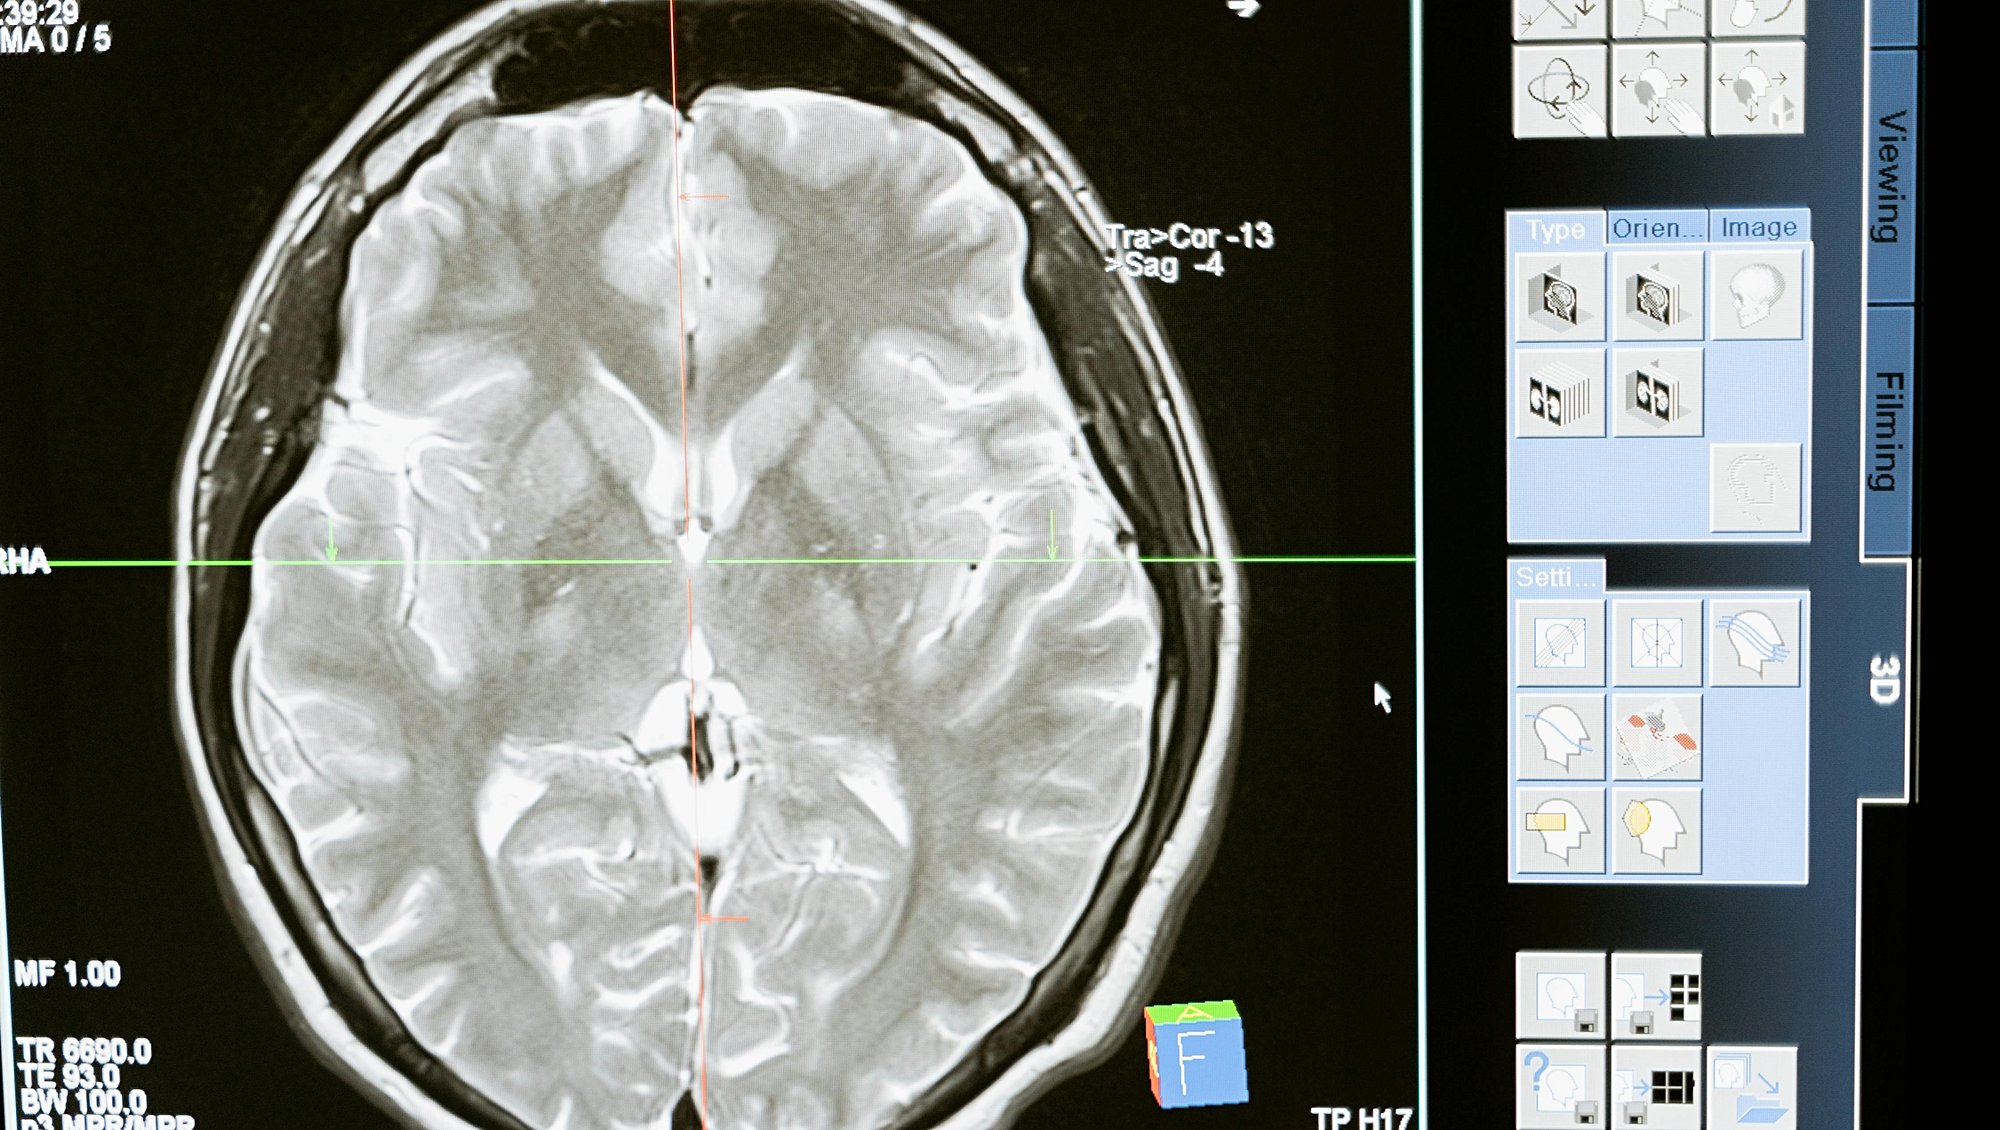

Beyin cerrahisi sırasında, beynin oksijen alımını sağlamak hayati bir öneme sahiptir. Kan akışı kesilirse veya yetersiz olursa, beyin hücreleri dakikalar içinde ölmeye başlar. Bu yüzden bir nöroşirürjiyenin en önemli görevlerinden biri, beyin kan akımını (CBF) ve serebral perfüzyon basıncını (CPP) cerrahi boyunca optimum seviyede tutmaktır.

Beyin cerrahisi sırasında kan akımının korunması, cerrahın en önemli sorumluluklarından biridir.

Beyin kan akımı (CBF) ve otoregülasyonu anlamadan yapılan ameliyatlar, ciddi komplikasyonlara neden olabilir.

CPP’nin dengede tutulması, beyin hasarını önler ve cerrahinin güvenli olmasını sağlar.

Hipoksi, hiperkapni ve yüksek ICP gibi durumları iyi yönetmek, ameliyat başarısını doğrudan etkiler.